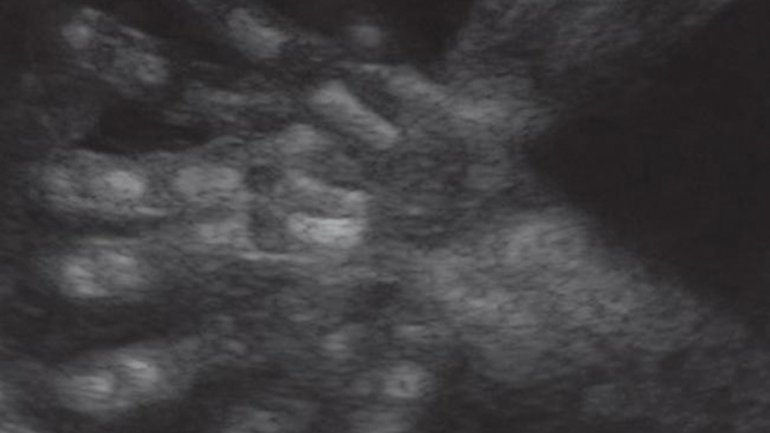

Ultraschall 11. SSW

Auf dem Ultraschallbild sieht man nur die Beine des Fötus. Sie sind an den Knien im rechten Winkel gebeugt, die Füße zeigen nach oben. Die Füße sind schon deutlich ausgebildet und in den Beinen sind die langen Röhrenknochen, in den Füßen die Knochen der Zehen gut zu erkennen.